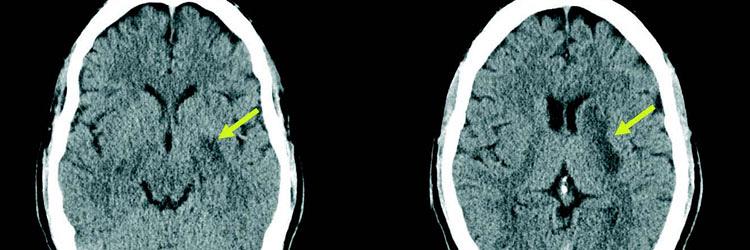

Looptraining na een CVA in de rechterhemisfeer Lees meer over Looptraining na een CVA in de rechterhemisfeer Looptraining na een CVA in de rechterhemisfeer

Als een fysiotherapeut looptraining geeft na een CVA in de rechterhemisfeer, dient hij rekening te houden met een aantal specifieke stoornissen die verband houden met een letsel in de rechterhemisfeer. Vanuit de probleemanalyse en de hulpvraag lijkt het aannemelijk om in een vroeg stadium het lopen te gaan trainen; dit beveelt de KNGF-richtlijn Beroerte ook aan. Bij deze casus blijken echter de problemen met het lopen op de loopband te verergeren terwijl het ‘gewone’ lopen goed gaat. Waarschijnlijk zijn deze problemen terug te voeren op angst en de moeite om nieuwe handelingen uit te voeren. Routinematige activiteiten die meer een beroep doen op de intacte linkerhemisfeer blijken gemakkelijker te gaan, bij deze patiënt het lopen in de duinen. Fysiotherapeuten dienen in hun behandelplan dus rekening te houden met de specifieke uitingsvormen van rechterhemisfeerproblematiek.